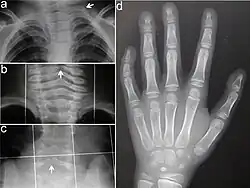

Typisch für das KBG-Syndrom sind faziale Dysmorphien (Gesichtsdysmorphien) und große obere mittlere Schneidezähne. Dazu kommen Anomalien des Skeletts, vor allem costovertebral, das heißt an den Rippenwirbeln, und eine verzögerte körperliche Entwicklung. Letztere führt zu Minderwuchs. Bei der Mehrzahl der Patienten finden sich außerdem EEG-Anomalien (mit oder ohne Krampfanfällen) und ein abnormer Haaransatz. Deutlich seltener sind kutane Syndaktylie, kurzer Hals mit Pterygium, Kryptorchismus („Bauchhoden“), Schwerhörigkeit, Schielen, Gaumendefekt und angeborene Herzfehler.[2]

Die Diagnosestellung erfolgt im Wesentlichen aufgrund der Symptome, da noch kein Gentest für das KBG-Syndrom verfügbar ist. Dabei orientiert man sich an vier wesentlichen Merkmalen des KBG-Syndroms: faziale Dysmorphie, Makrodentie der oberen mittleren Schneidezähne, skelettale Anomalien (vor allem costovertebral) und verzögerte Entwicklung. Im Alter von sieben bis acht Jahren lässt sich mit der Ausbildung der vorderen Schneidezähne über die Makrodentie die Diagnose sicherer erstellen.[2]